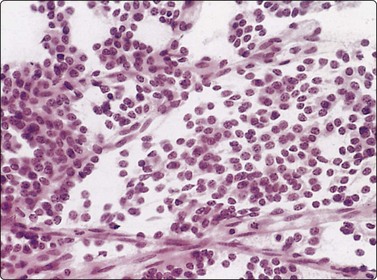

image image

Fig. 8.33 Carcinoid tumor

(A) Plexiform aggregate of small blood vessels with adherent tumor cells (Pap, LP); (B) Aggregate of small regular cells with stippled neuroendocrine nuclear chromatin pattern (Pap, HP).

image

Fig. 8.34 Carcinoid tumor

Dispersed regular tumor cells in company with small capillary blood vessels (H&E, HP).

image image image

Fig. 8.35 Carcinoid tumor, spindle cell type

Tight aggregate of spindle cells with little pleomorphism. Cell block showing no mitotic activity or necrosis. Strong positive immunostaining for synaptophysin (A, H&E, HP; B, Cell block, H&E, HP; C, Cell block, IPOX, HP).

In ‘classic’ carcinoid tumors, the FNB findings are often distinctive enough to permit diagnosis, with or without ancillary tests such as immunocytochemistry. In contrast, the atypical carcinoids that we have seen were more difficult to classify before resection. Nicholson et al. found similar problems in recognizing a proportion of their neuroendocrine carcinomas, including low- and high-grade tumors, and suggested that ‘attention to the presence of loose cell aggregates in a background of singly dispersed cells; feathery patterns created by tumor cells clinging to capillaries; rosette formations; delicate, granular cytoplasm; inconspicuous nucleoli; molding in high-grade tumors; and, most importantly, speckled or dusty chromatin patterns are useful in identifying neuroendocrine differentiation in cytologic specimens’.36